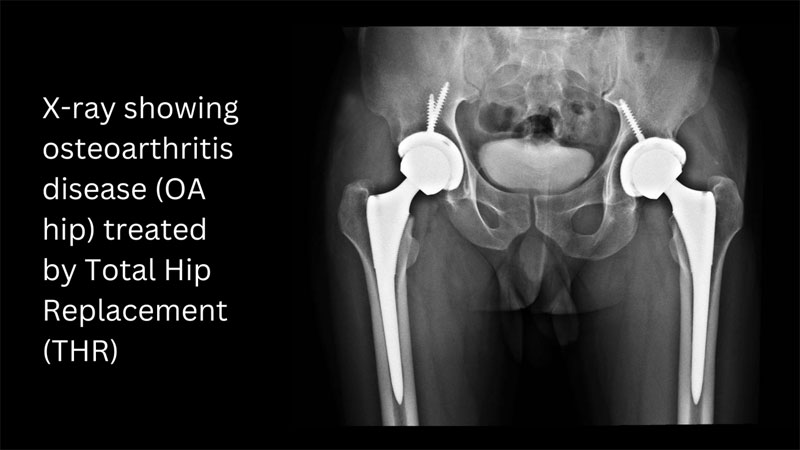

Hip pain and joint degeneration can be incredibly debilitating, affecting your ability to move freely and enjoy life to the fullest. When conservative treatments fail to provide relief, hip replacement surgery becomes a viable option to restore mobility and reduce pain. Anterior hip replacement is a modern approach to this procedure that offers several advantages over traditional methods. In this blog, we'll explore what you need to know about anterior hip replacement.

Anterior hip replacement is a surgical procedure used to replace a damaged or degenerated hip joint with an artificial implant. What sets it apart from traditional hip replacement techniques is the surgical approach. In anterior hip replacement, the surgeon accesses the hip joint from the front of the body, as opposed to the side or back, which is more common in traditional approaches.

● Osteoarthritis

● Preparation: You will undergo a thorough pre-operative evaluation, which may include imaging tests like X-rays and MRI scans. Your surgeon will discuss the procedure, address your questions, and give you pre-operative instructions.

● Implant Placement: The damaged portions of the hip joint are removed, and the artificial implant is securely placed into the bone. This implant typically includes a metal stem, a metal or ceramic ball, and a plastic socket.